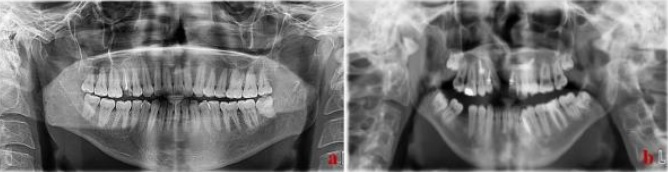

Bu çalışma, 2018 yılı içerisinde Eskişehir Osmangazi Üniversitesi, Diş Hekimliği Fakültesi hastanesine gelen hastalardan elde edilen görüntülerin sınıflandırılmasından oluşturduğunuz veri seti ile gerçekleştirilmiştir. Veri seti düzenlemeden önce belirli bir anlam düzeyinin üzerinde yer alan gürültü, belirsizlik, bozulma ve gölgeler değerlendirmeye alınmamıştır. Veri seti eksik diş tespiti için 99 tam diş ve 54 eksik diş olmak üzere 153 görüntüden oluşmaktadır. Tüm görüntüler uzman diş hekimleri tarafından tekrar kontrol edilmiş ve doğrulanmıştır. Resim 1’de

eksik ve tam diş görüntüleri yer almaktadır.

Resim 1..a: Bütün dişlerin mevcut olduğu hastasının panoramik radyografisi b: Eksik dişlerin varlığında hastanın panoramik radyografisi